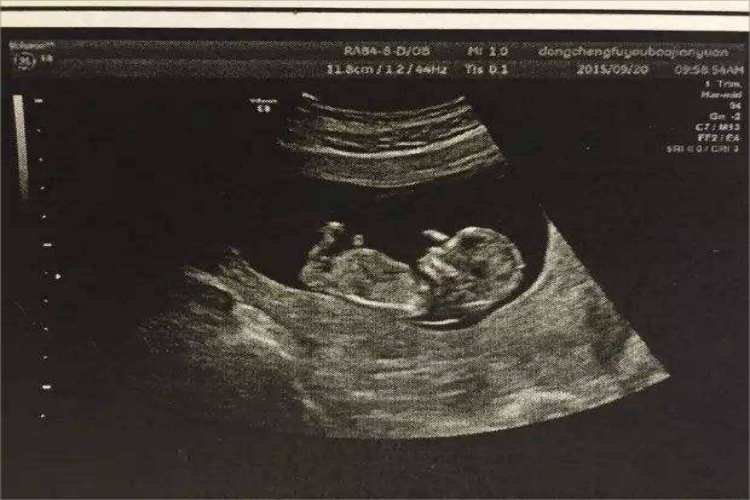

- 孕9-12周:随着孕周的增加,胚胎逐渐发育成胎儿。到孕12周左右,胎儿已经基本成型,可以清晰地看到头部、四肢和脊柱等结构。此时胎儿的五官也已经初步发育完成,外生殖器也开始发育。孕妇此时还会有早孕反应,如恶心、呕吐等。